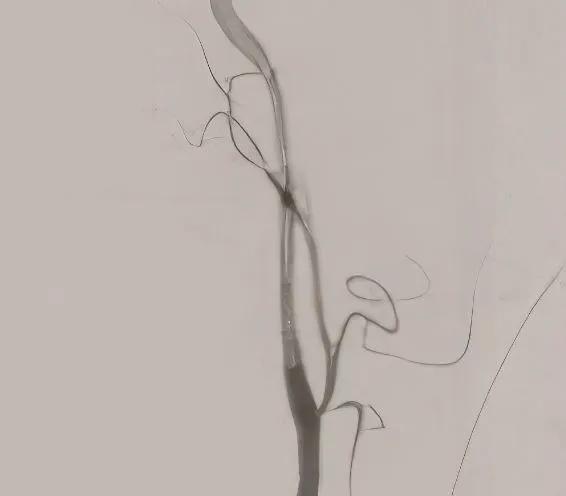

Robotic-assisted valve surgery provides the surgeon with an undistorted, three-dimensional view of the valve, leaflets and subvalvular structures using a special camera. This approach enables surgeons to perform complex mitral valve repairs or valve replacements without the need for division of the breastbone (sternum) or spreading of the ribs.

The surgeon uses a specially designed computer console to control surgical instruments on thin robotic arms. The robotic arms are introduced through a 1- to 2-inch incision in the right side of the chest. The surgeon’s hands control the movement and placement of the endoscopic instruments to open the pericardium and perform the procedure. The enhanced view of the anatomy provided by the specialized camera makes the surgical process easier. Surgeons can access the heart valves with greater precision and less of a physical impact on the patient, which allows for considerably lower time in post-op than with most procedures.